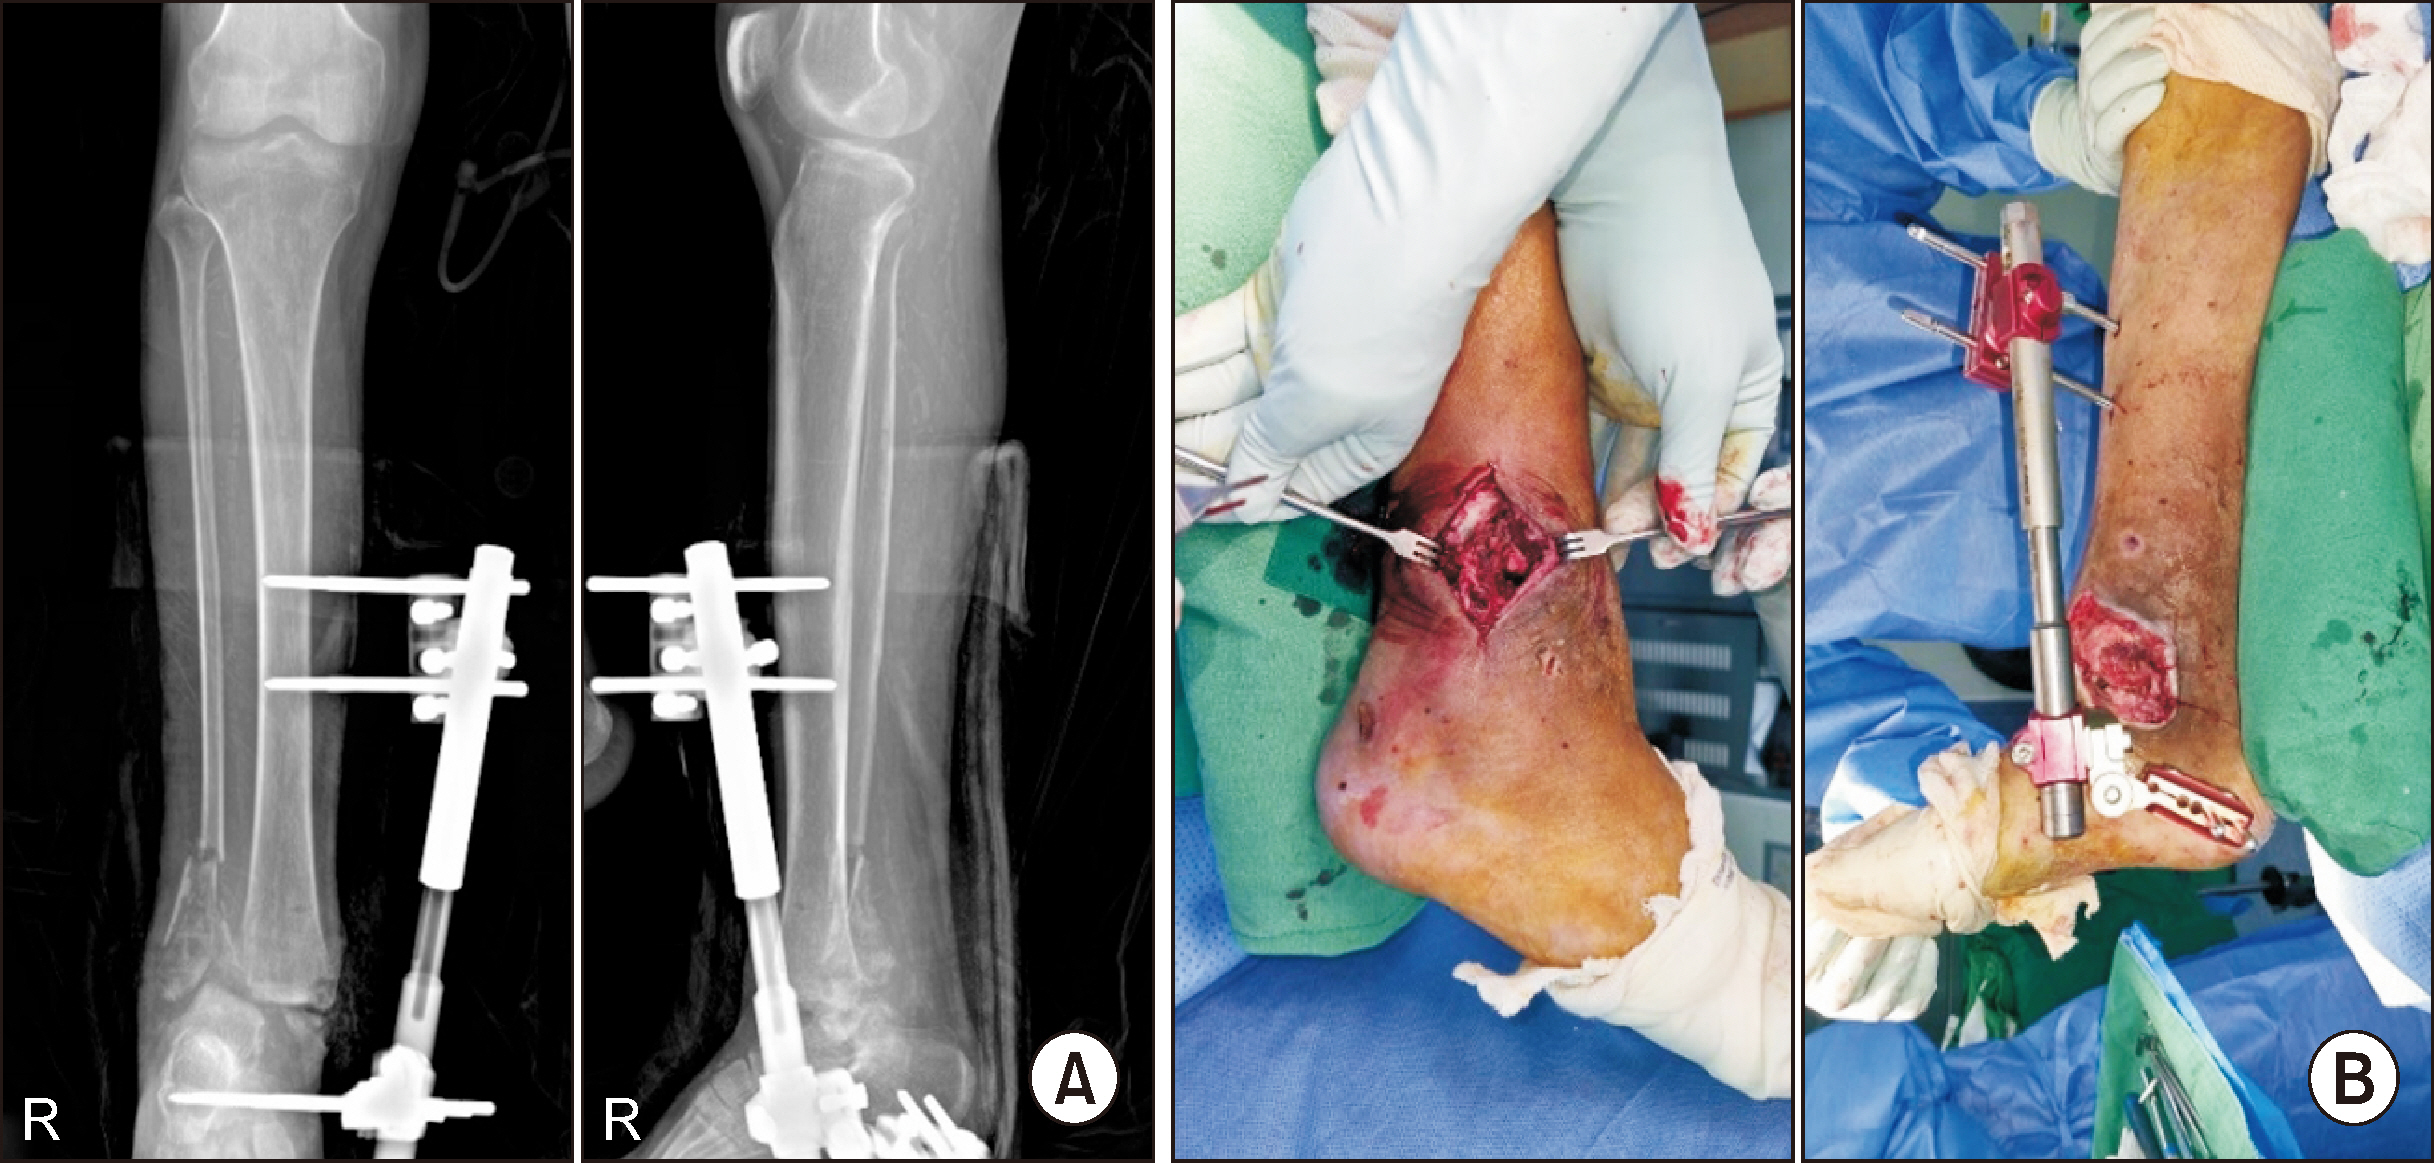

Charcot neuroarthropathy (CN), also known as Charcot arthropathy, is a complex, progressive disorder primarily affecting the foot and ankle. This case report describes a multifaceted management strategy for a 54-year-old male with diabetes mellitus, end-stage renal disease, and presumed underlying Charcot arthropathy who experienced a traumatic ankle fracture. The initial surgical plans were delayed because of systemic infection indicators, including elevated C-reactive protein levels and high fever. The patient underwent multiple surgical interventions and faced challenges, including metal failure, implant-associated infection, and tibiotalar joint dislocation. A multidisciplinary approach involving orthopedic surgeons, nephrologists, and endocrinologists was crucial for managing the case effectively. In particular, the patient declined a below-knee amputation and opted for comprehensive surgical intervention, resulting in improved functionality at the latest follow-up. This case highlights the complexities of managing CN in patients with multiple comorbidities and emphasizes the need for a nuanced, patient-centered approach.